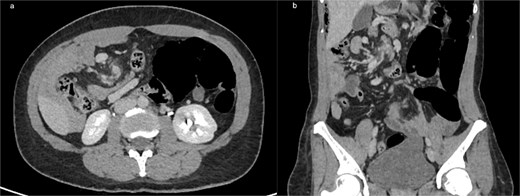

(a) Axial contrast-enhanced CT showing the classic ‘whirlpool sign,’ with clockwise swirling of the superior mesenteric vein and mesenteric fat around the SMA, consistent with midgut volvulus (b) coronal CT reconstruction confirming mesenteric torsion.